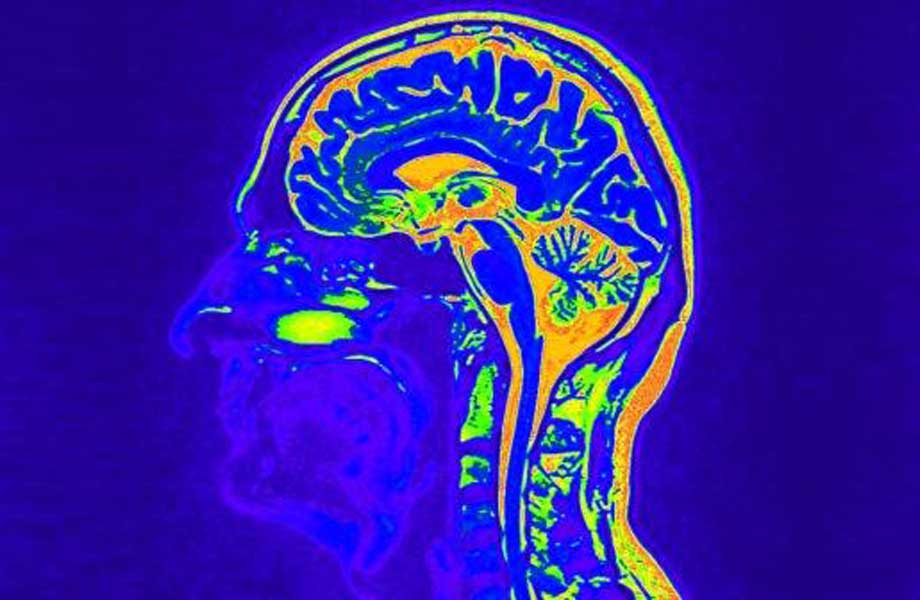

Die Entwicklung des CGRP-Antagonisten MK-0974 (Telcagepant) wurde fortgeführt. Der Wirkstoff Telcagepant eröffnete die Option für einen klinisch anwendbaren CGRP-Rezeptorantagonisten in der Migräneakuttherapie. Er besitzt eine neuartige Wirkungsweise indem er einerseits Migräneattacken kupieren kann, andererseits jedoch nicht zu einer Gefäßverengung führt und auch nicht über den Serotoninmechanismus funktioniert. CGRP und seine Rezeptoren werden in vielen Bereichen des Gehirns gefunden. CGRP nimmt in der Weiterleitung von Migräneschmerzen nach aktuellen Forschungsergebnissen eine entscheidende Rolle ein. Während der Migräneattacke bindet CGRP an den CGRP-Rezeptoren und aktiviert diese. Dadurch werden Schmerzsignale weitergeleitet. MK-0974 (Telcagepant) ist in der Lage, CGRP an den Rezeptoren zu blockieren und kann dadurch die Übertragung von Schmerzsignalen und Migräneattacken stoppen.